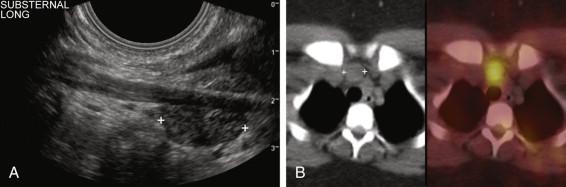

Ectopic locations are encountered in approximately 3% of patients ( Box 10-3 ). The retrotracheal region is a common site for ectopic superior adenomas. These can be difficult to visualize sonographically due to their deep location and gas shadowing from the trachea. To counteract this, the patient's head should be turned to the opposite side and scanning should be performed from a lateral location with the transducer angled medially. Lower-frequency curved-array probes with a short radius of curvature are also helpful in detecting deep adenomas. Probes designed for neonatal heads or transvaginal scanning are very small and often work very well in looking deep into the neck ( e-Fig. 10-5 ). Ectopic parathyroid adenomas can also be located in the carotid sheath ( Fig. 10-22 ) or in the thyroid ( Fig. 10-23 ). Intrathyroidal adenomas are easy to see sonographically but can be easily confused with thyroid adenomas or other thyroid nodules. They can occur in any part of the thyroid but are usually located in the posterior half. They have sonographic features similar to other parathyroid adenomas. The superior mediastinum is a well-recognized but very uncommon location for ectopic adenomas. When in the mediastinum, they are usually anterior and related to the thymus, although they can occur posteriorly and as low as the aortopulmonary window. Mediastinal adenomas are difficult to visualize with sono­graphy because high-frequency linear-array transducers that are typically used have limited penetration and are often too large to manipulate in the relatively confined suprasternal and supraclavicular regions. As with deep lesions in the neck, tightly curved array probes can assist in visualizing superior mediastinal adenomas ( Fig. 10-24 ). Approximately 5% of patients with hyperparathyroidism have multigland disease ( e-Fig. 10-6 ). Multigland involvement is considerably more difficult to detect with all imaging modalities.

F igure 10-24, Ectopic parathyroid adenoma in the mediastinum. A, Longitudinal view of the inferior neck and the superior mediastinum using a transvaginal probe shows a parathyroid adenoma (cursors) in the substernal region. B, Sestamibi scan confirms a superior mediastinal adenoma (cursors) .